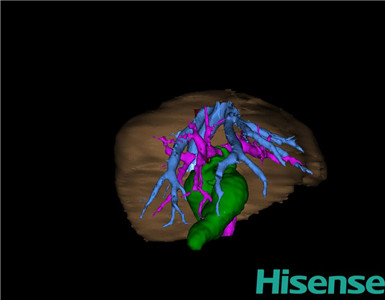

CT结果输入海信CAS系统后行3D重建及手术规划后,于2015-11-18全麻下行“胆总管囊肿切除+胆囊切除+胆总管-空肠吻合术”手术治疗:

将0.625mm双源薄层CT资料的静脉期和动脉期Dicom格式文件导入海信CAS系统。

通过调节窗宽窗位调整CT序号,对肝实质,胆囊,胆总管,下腔静脉,肝动脉、门静脉及肝静脉等进行三维重建;系统自动计算肝脏体积。

术前手术方案的规划。

术前三维重建:

重建图片